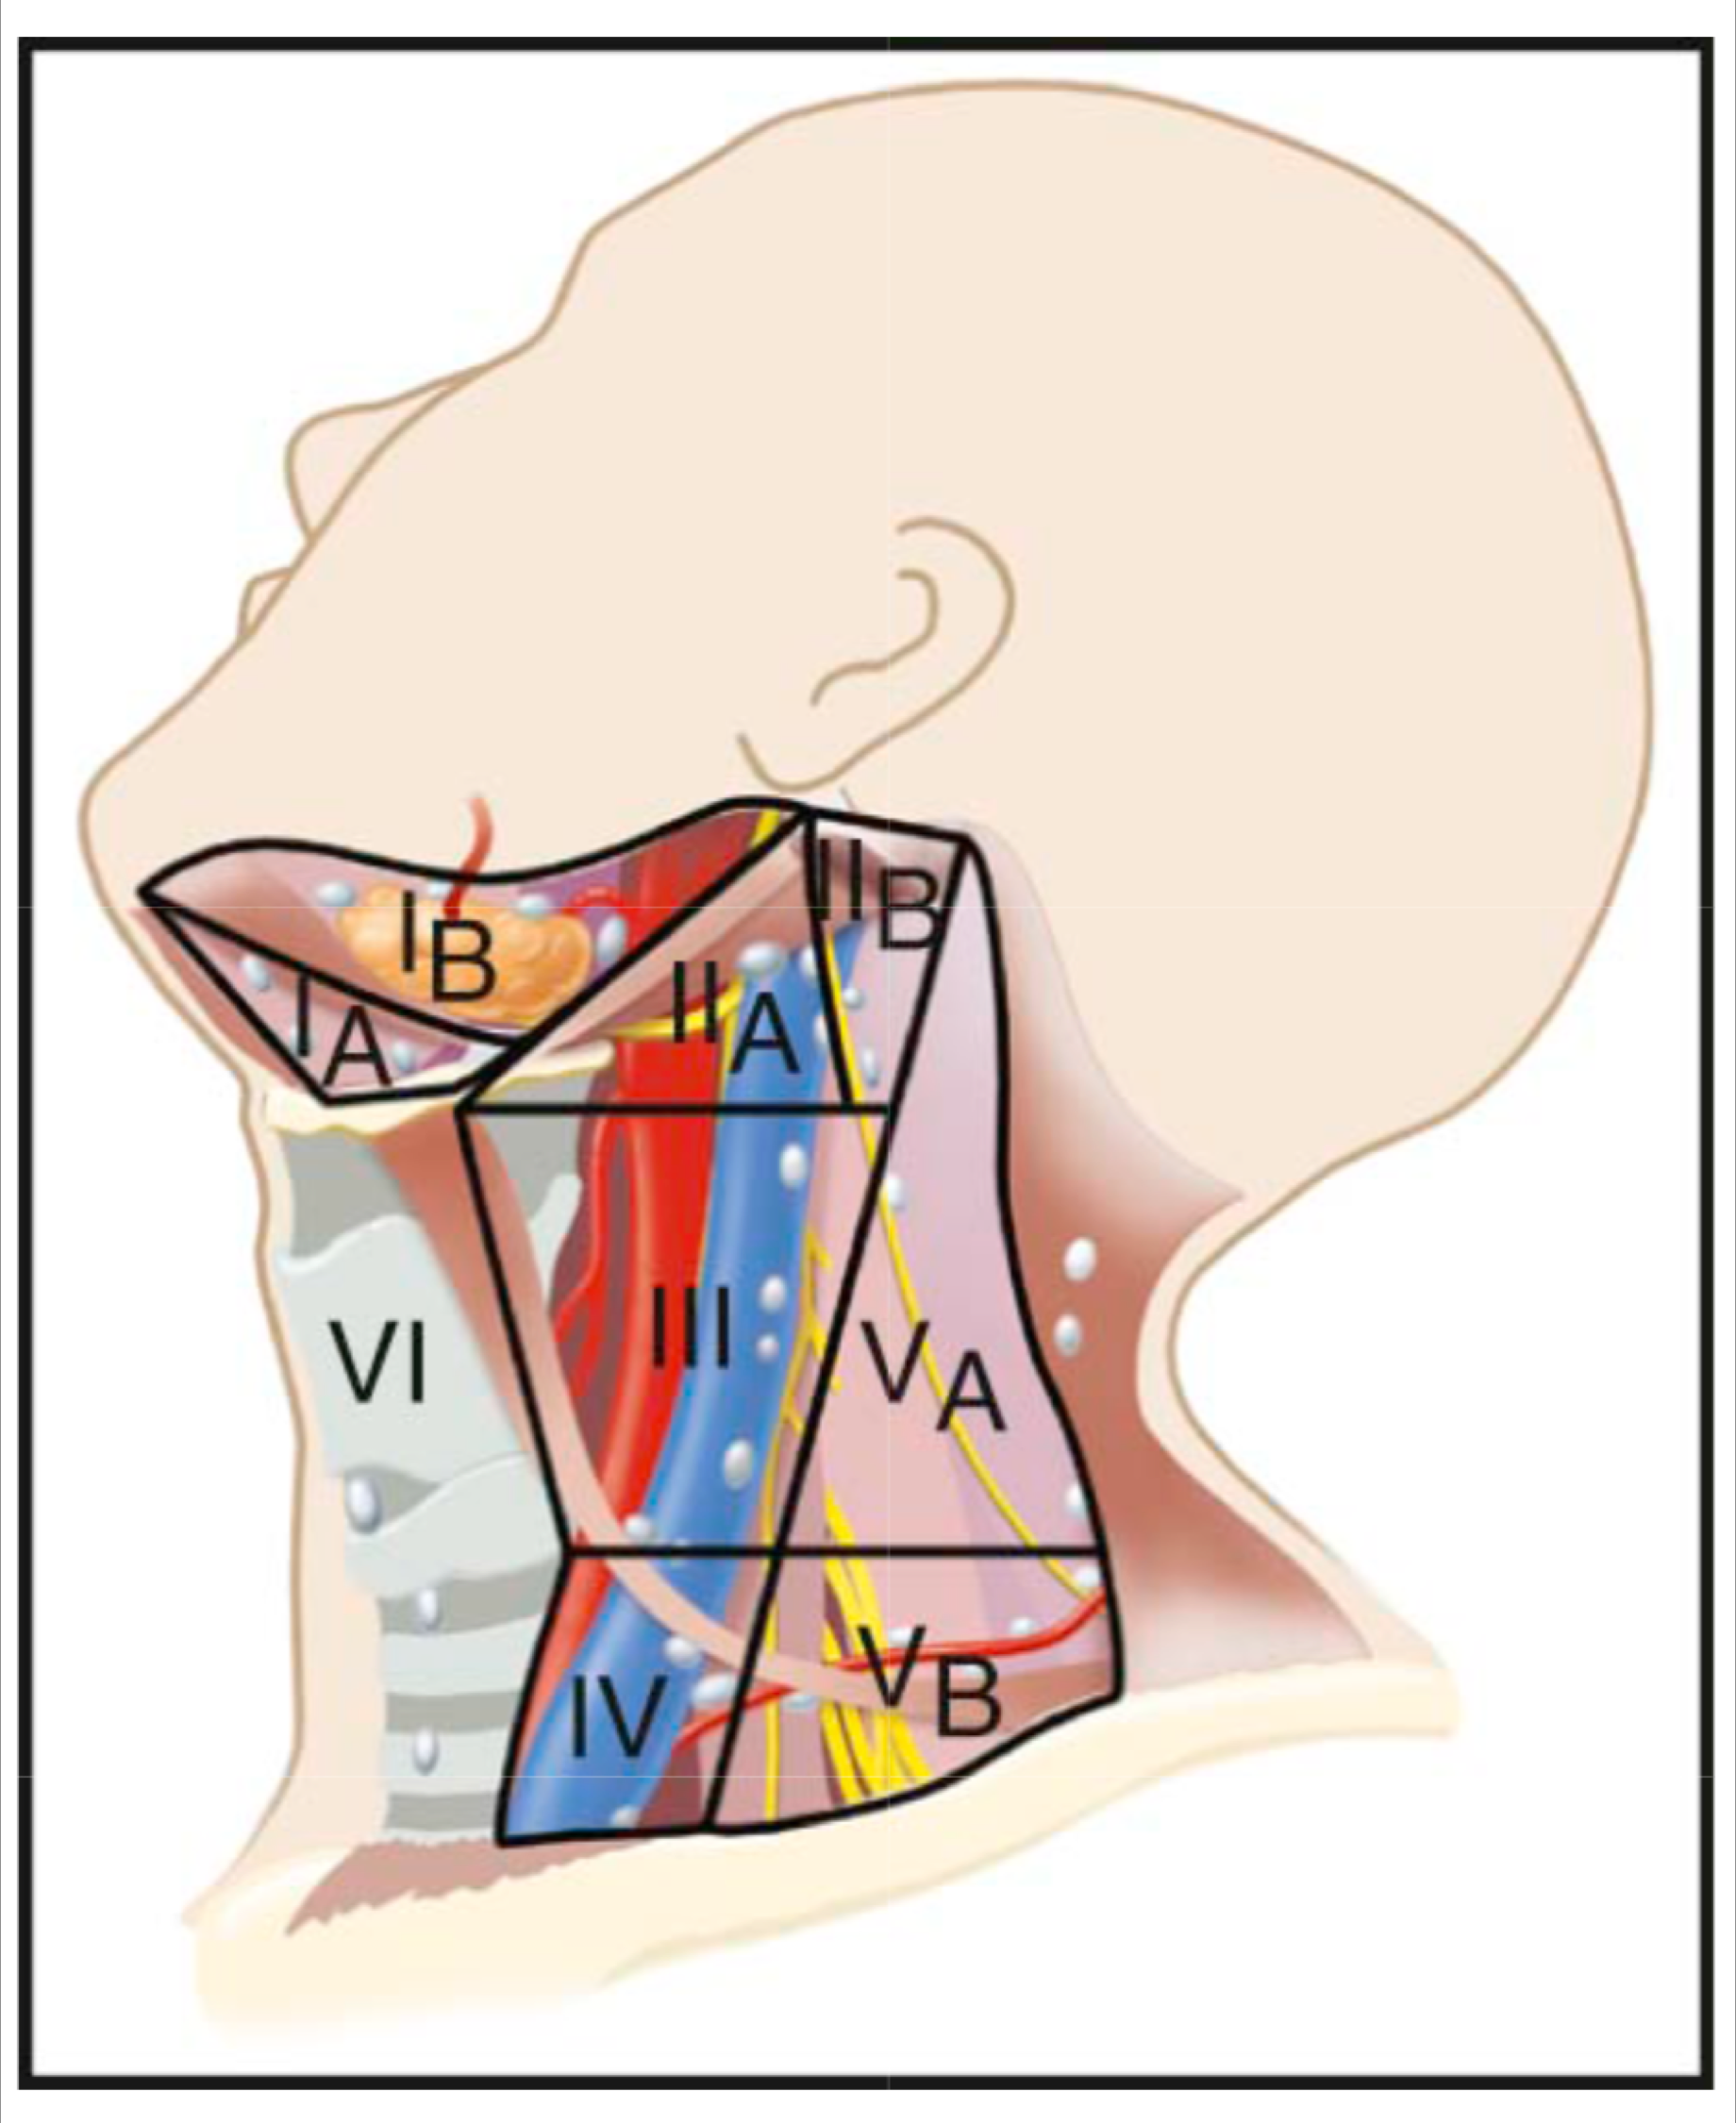

Lymphatic system

總圖

Nodes

Groups

- Level I

- the submental group (Ia), and the

submandibular group (Ib). - Level II

- the upper jugular lymph nodes

- level IIa – CN XI 前

- level IIb – CN XI 後

- Level III

- the middle jugular lymph nodes

- Level IV

- the lower jugular lymph nodes

- Level V

- all lymph nodes contained within the posterior triangle

- Level VI

- lymph nodes of the anterior (central) neck compartment